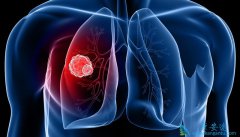

肺癌刚刚开始的时候都是咳嗽,与偶的人咳嗽的厉害的时候还会有咳血的症状,通常都是这个时候才会引起重视,到医院去检查的,而很多人都是拖到咳血,胸痛难忍吃药也比起多大的作用的时候才去医院检查的,到医院检查就是 肺癌晚期 。可能很多人想要知道 肺 ...